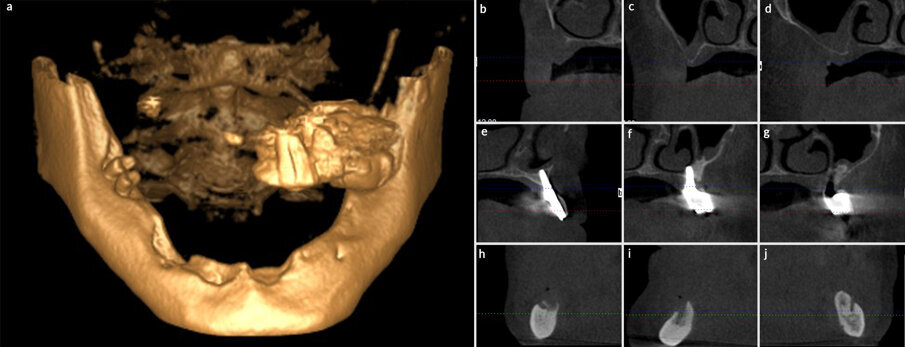

Un paziente di sesso maschile di 44 anni giunge alla nostra clinica privata dopo essere stato inviato da una collega dentista per la valutazione del caso e la proposta di un piano di trattamento. Il paziente riferisce di vivere una situazione di estremo malessere a causa delle condizioni della sua bocca (Figg. 1-3), di aver perso degli impianti precedentemente inseriti e riabilitati con ponti definitivi avvitati (sia nell’arcata superiore che in quella inferiore), e di essersi precedentemente recato in altri studi odontoiatrici, nei quali gli era stato detto che il suo caso necessitava di tecniche avanzate di chirurgia implantare. Grazie a un’esplorazione clinica e un’analisi mediante ortopantomografia e CBCT (Fig. 4), osserviamo che il paziente, dopo la perdita degli impianti pre-esistenti, è parzialmente edentulo nell’arcata superiore, dove conserva solo un ponte avvitato su quattro impianti nel secondo quadrante (che mostrano condizioni pessime dell’osso periimplantare), e totalmente edentulo nel mascellare inferiore. Si evidenziano, inoltre, la quasi totale assenza di osso residuale nel mascellare superiore, con la presenza di una comunicazione oro-antrale nella zona anteriore del primo quadrante e di importanti difetti ossei nella mandibola; in quest’ultima non esiste altezza ossea posteriore adeguata per la collocazione di impianti, e il forame mentoniero è superficiale nel terzo quadrante e crestale nel quarto quadrante. Si propone al paziente un trattamento di riabilitazione con 4 impianti zigomatici nel mascellare superiore (Zygoma Quad) (Fig. 5) e 4 impianti convenzionali (2 dritti e 2 inclinati) nel mascellare inferiore. L’intervento si svolge in anestesia locale e sedazione cosciente. Nel mascellare superiore, si provvede alla rimozione degli impianti rimanenti, alla dissezione del tessuto infiammatorio e infetto circostante e all’inserimento dei 4 impianti zigomatici mediante la tecnica anatomy-guided descritta da Aparicio et al7 , per cercare un tragitto dell’impianto che permetta di ottenere un’emergenza quanto più crestale possibile (essendo questo un fattore favorevole sia biomeccanicamente sia in relazione al comfort del paziente).

Fig. 4 - Tagli del CBCT. 4a: ricostruzione 3D dei mascellari, dove si evidenziano l’atrofia completa e la totale assenza di anatomia del primo quadrante. 4b: primo quadrante zona premascellare, dove si osserva una comunicazione oro-antrale. 4c: primo quadrante zona premolare. 4d: primo quadrante zona molare. 4e: secondo quadrante zona premascellare. 4f: secondo quadrante zona premolare. 4g: secondo quadrante zona molare. 4h: forame mentoniero quarto quadrante. 4i: zona mandibolare anteriore. 4j: forame mentoniero terzo quadrante.